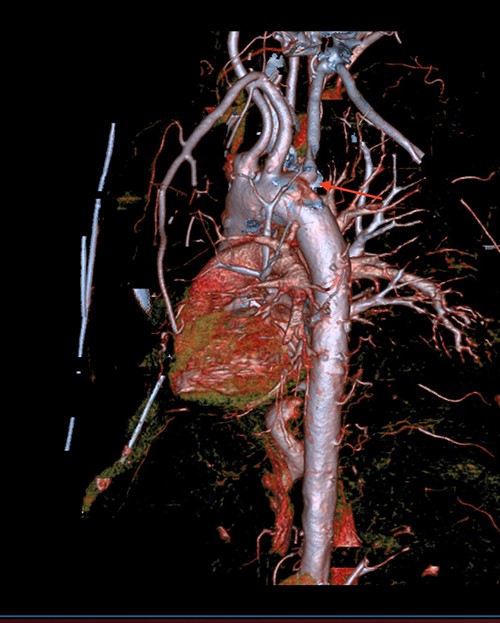

A 71-year-old male with past medical history of type 2 diabetes and hypertension presented to the emergency department at St. Joseph’s University Medical Center with severe respiratory distress. On nonrebreather, the patient’s oxygen saturation was 49%. The patient was subsequently intubated. Evaluation revealed pneumonia secondary to COVID-19 leading patient to be intubated on ventilator support for 4 weeks. During this time patient was maintained on enteral feeding through nasogastric tube, and was on gastrointestinal prophylaxis Protonix 40 mg daily for the duration of his admission. Ultimately, the patient made full recovery and was sent home; however, approximately 3 weeks later, he presented to the emergency department due to syncope. The patient experienced large-volume bright red hematemesis. He became hypotensive and was transfused three units of packed red blood cells and started on pressors. The patient was intubated and transferred to the intensive care unit (ICU) with acute blood loss anemia and hypovolemic shock. Here, an esophagogastroduodenoscopy (EGD) was performed revealing midesophageal bleed (Fig. 1). Hemostasis was achieved with clipping; however, post-procedurally, the patient again became hypotensive. Repeat EGD showed a nonbleeding esophageal ulcer with three clips in good position (Fig. 2). Computed tomography (CT) angiogram of the thorax was performed revealing an actively bleeding aberrant right subclavian artery perforating into the esophagus (Figs 3 and 4). The right subclavian artery was noted to be of normal caliber without ectasia or aneurism and the esophagus was free of any other pathology. Thoracic and vascular surgery were consulted; however, the bleed was deemed of nonsurvivable pathology due to comorbidities and current clinical status. Ultimately, the family of the patient decided to withdraw care and the patient passed.

CT thoracic angiogram showing actively bleeding aberrant right subclavian artery perforating into the esophagus (red arrow).